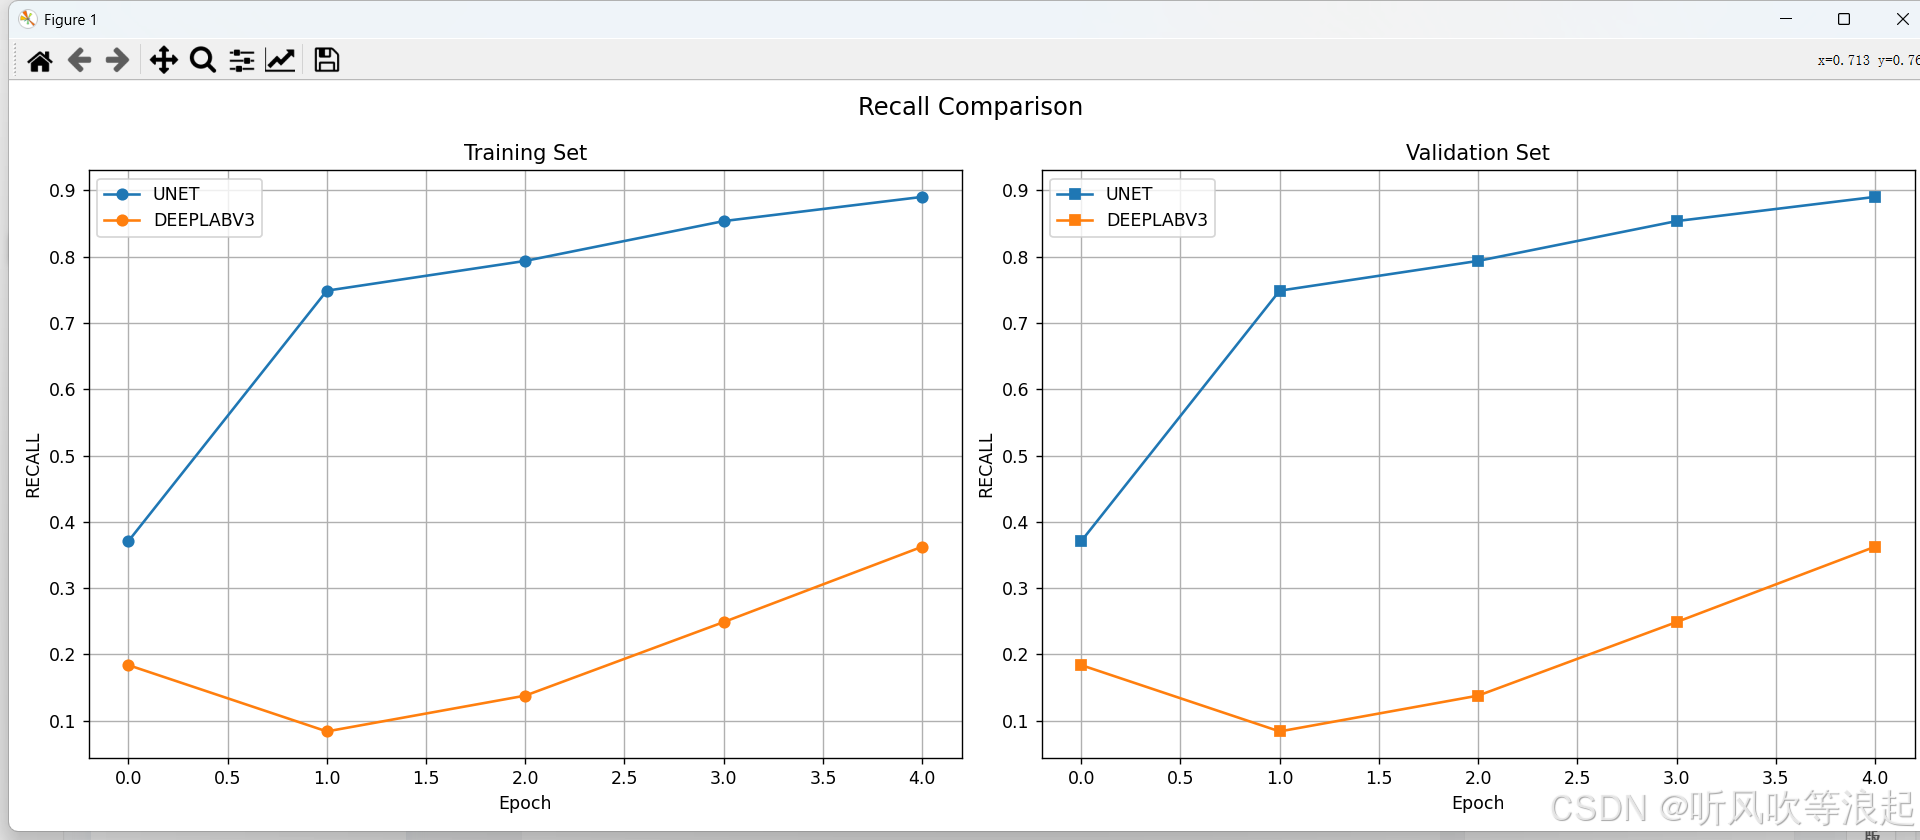

通过可视化工具可以直观比较不同模型的性能表现:

ax2.plot(epochs, values, label=model_name.upper())可视化结果通常显示:

- UNet在小数据集上通常收敛更快

- DeepLabV3在大数据集上表现更优

- 两种模型在不同指标上的曲线

这里仅仅训练了5个epoch用于测试代码的可行性,指标不做参考

3.对比